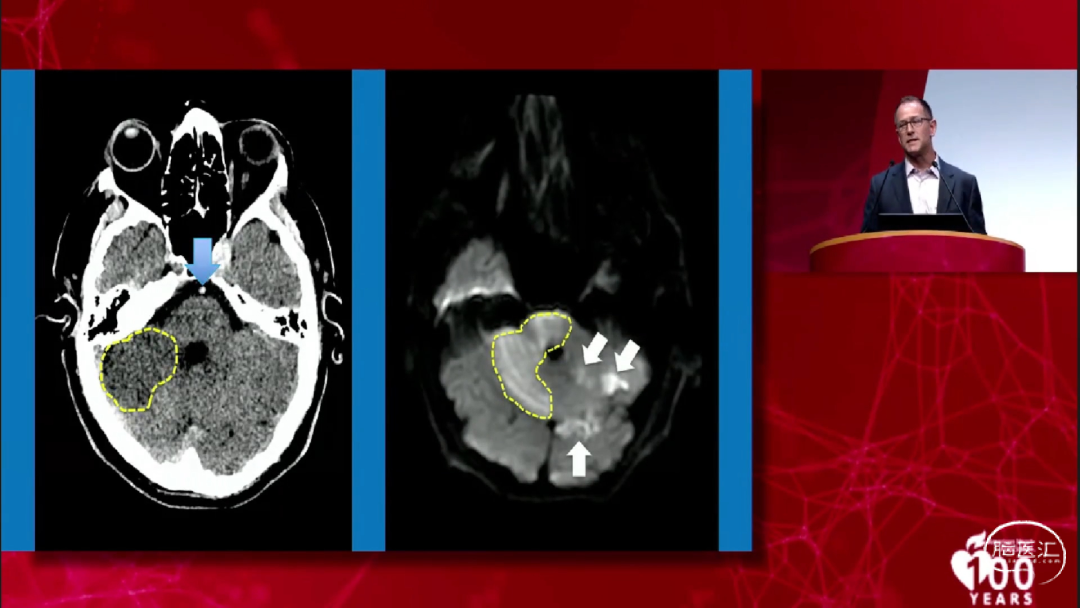

MRI DWI序列更加清晰和准确,尤其在以下这个例子中显示的更加明显:这是一个基底动脉闭塞患者的NCCT,在右侧小脑半球可以看到明显的低密度,但是同时做的MRI DWI序列却显示了完全不同的核心梗死部位。MRI DWI序列的优点很明显,但是在大多数中心急诊MRI并不是常规检查。